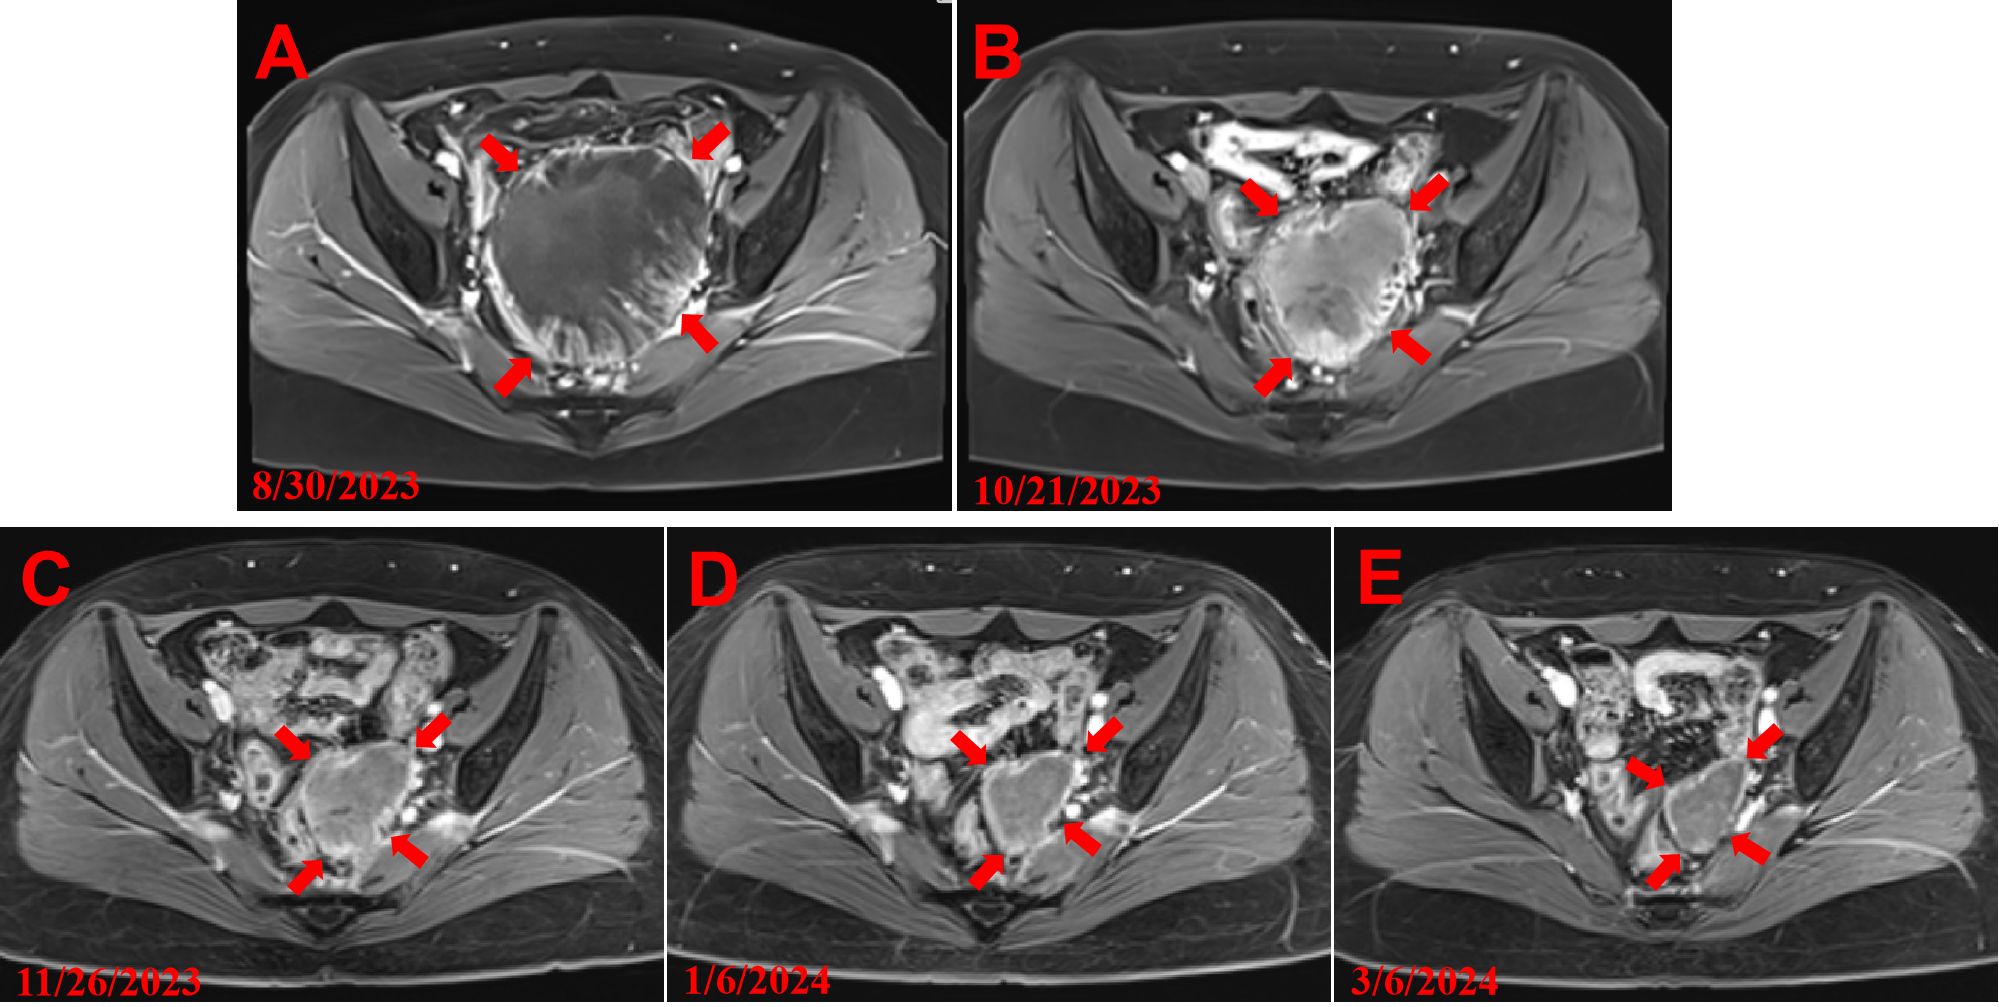

Background Surgery is the primary treatment for Endometrial Stromal Sarcoma (ESS), however, a substantial proportion of patients with ESS experience recurrence or metastasis. Currently, surgery and local ablation are the main treatments for recurrent ESS followed by chemotherapy, radiotherapy, immunotherapy, targeted therapy, and anti-estrogen therapy. Surgery and local ablation are invasive treatments and may carry risks such as intestinal damage and the risk of massive bleeding from tumor rupture. For patients who refuse or are unable to undergo surgery and local ablation, conservative treatment is not effective, and there is currently no definitive effective non-invasive or combined treatment plan. Case presentation This report presents a case of a patient with recurrent endometrial stromal sarcoma who refused surgical and local ablation treatments. After receiving HIFU treatment combined with chemotherapy, the progression of the tumor was effectively inhibited, the tumor volume significantly reduced, and liver function was restored during the HIFU period, providing an opportunity for chemotherapy. Conclusions HIFU combined with chemotherapy may provide a new treatment strategy for patients with recurrent, metastatic endometrial stromal sarcoma, or those who are unsuitable for surgery, local ablation, or those with poor baseline status unable to tolerate intensive chemotherapy.